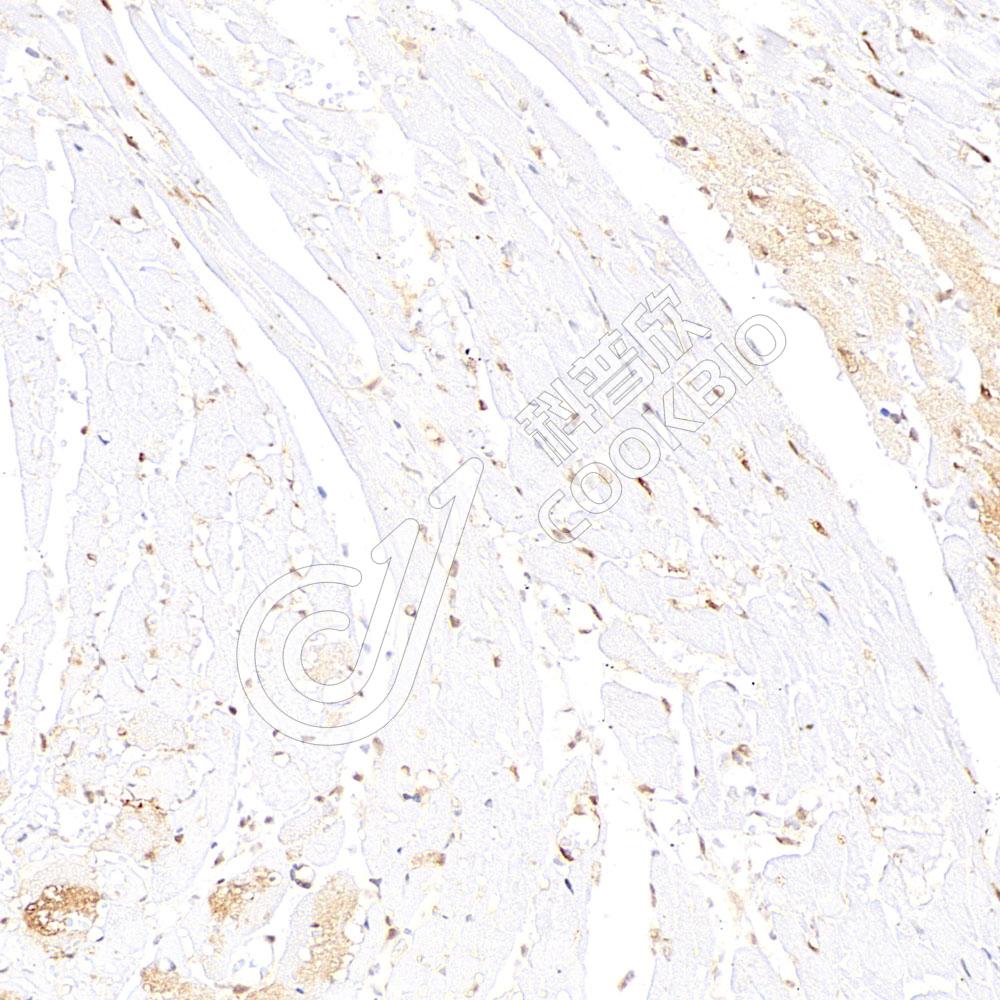

IHC检测Hsp70蛋白(货号 K545732).

样品: 小鼠心脏缺血再灌注损伤, 4%多聚甲醛 (货号KSG1101) 固定12-24小时.

抗原修复: 柠檬酸抗原修复液(干粉, pH 6.0) (KSG1201), 高压锅均匀喷气计时2分钟.

—抗: 1: 800稀释, 4℃ 孵育过夜.

二抗: S-vision免疫组化多聚二抗(山羊抗兔),即用型 (货号KB3906), 室温孵育20分钟.